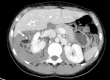

We report the case of a 29-year-old woman with Wunderlich syndrome, a rare spontaneous renal hemorrhage into the subcapsular and perinephric space. She presented to our emergency department with a sudden and persistent right flank pain in the abscence of abdominal injury. The onset of the symptoms can be insidious and lead to hypovolemic shock. Computed Tomography helps both in the diagnosis, detecting the renal hemorrhage, and contributes to an optimal patient management. Selective arterial embolisation is an efficient technique to stop acute and potential life-threatening hemorrhage and preserve the renal parenchyma.